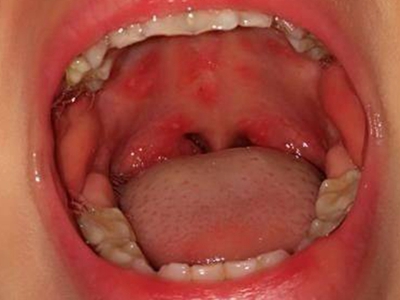

口腔

溃疡

口腔手足口病图片

手足口病累及口腔上颚部位时,局部出现圆形疱疹,疱壁较薄,很容易发生破溃形成溃疡,表现为圆形的乳白色糜烂面,周围绕有红晕,由于存在疼痛感,儿童患者可有食欲不振、哭闹拒食的行为。

红点 · 溃疡

手足口病嘴里长了好多小红点图

手足口病患者口腔内,尤其是上颚部位出现密集的红色丘疹损害,数量较多,个头不大,类似小红点,多散在分布,偶见融合现象,周围黏膜存在明显的充血红肿表现,部分皮损破溃后形成溃疡。